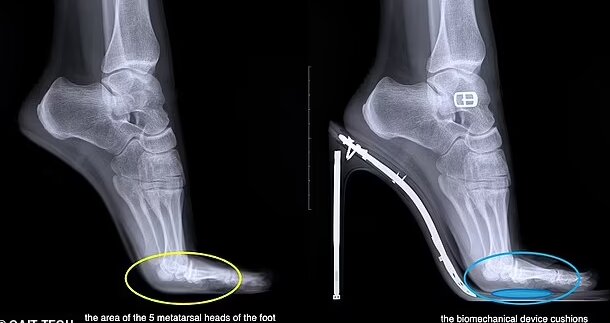

کفشهای پاشنهبلند، تمام وزن کاربر را روی قسمت جلوی پا قرار میدهند و فشار شدیدی را بر انتهای استخوانهای کف پا و مفاصل بین انگشتان و پا وارد میکنند. این امر به افزایش خطر شکستگی استخوان، ضخیم شدن بافت اطراف عصب پا و سایر آسیبهای احتمالی منجر میشود.

این کفی که توسط شرکت ایتالیایی «GAIT-TECH» ساخته شده است، ضربه را هنگام راه رفتن از بین میبرد و فشار را در سراسر پا پخش میکند. این کفی در دید نیست و به طور ناخوشایند زیر پا تکان نمیخورد.